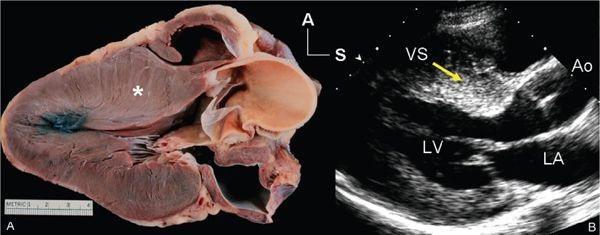

- تنگی دریچه آئورت، یا باریک شدن دریچه آئورت که بخش زیرین سمت چپ قلب را از آئورت (رگ بزرگ خارج شده از سمت چپ قلب) جدا میکند.

- ضخیم شدن بخش زیرین قلب (کاردیومیوپاتی هیپرتروفیک)، که ممکن است از بدو تولد وجود داشته باشد یا به مرور زمان ایجاد شود.

اگر بیماری قلبی مادرزادی تشخیص داده نشود و درمان نشود، خطر ایست قلبی در شما افزایش مییابد. اما حتی با وجود درمان، بیماری قلبی مادرزادی که ساختار قلب شما را تحت تأثیر قرار میدهد ممکن است خطر باریک شدن رگها و حمله قلبی را افزایش دهد. دکتر فینک بیان میکند: «در این موارد ممکن است مشکلی در ساختار قلب شما وجود داشته باشد که باعث کاهش جریان خون به قلب میشود. این شرایط نادر هستند، اما احتمالاً همانهایی هستند که بیشتر افراد هنگام فکر کردن به کاهش جریان خون و مرگ ناگهانی نگران آنها هستند.»